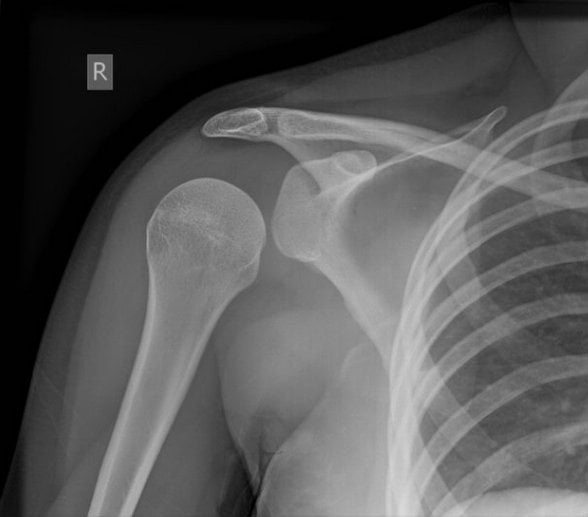

Для подтверждения диагноза проводится рентгенография, а при необходимости — МРТ. Терапия заключается в закрытом или открытом вправлении плечевого сустава, ношении повязки Дезо. На этапе реабилитации пациентам показаны физиопроцедуры, массаж, занятия лечебной физкультурой.

Довольно часто диагностируется сочетание вывиха с травмированием других суставных структур. Это перелом головки, отрыв одного из бугорков кости плеча, перелом впадины сочленения или отростков лопатки (акромиального, клювовидного).

| Формы вывиха плечевого сустава | Характеристика повреждения |

| Передний | Диагностируется в 95% случаев всех вывихов плеча. Плечевая кость смещается кпереди в нижнюю часть клювовидного отростка. Ее головка полностью утрачивает контакт с лопаткой. К вывиху такого вида приводит непрямое травмирование руки, которая в момент повреждения находится в разогнутом положении. Переднее смещение кости провоцирует также прямое механическое воздействие на нее, например, сильный удар сзади |

| Задний | Головка плечевой кости смещается кзади в результате механического воздействия на переднюю область сочленения. В редких случаях задний вывих происходит из-за удара в места, расположенные поблизости плеча — предплечье, локоть, кисть. К заднему смещению костной головки приводит удар в сустав, находящийся в согнутом положении при его вращении |

| Нижний | Самой редкой считается форма вывиха, при которой костная головка смещается вниз относительно лопатки. Сустав травмируется вследствие механического воздействия в положении отведения, например, при поднятии руки вверх. Итогом становится смещение плечевой кости под впадину сочленения с фиксацией конечности в патологической позиции — поднятой над головой. Нередко при нижнем вывихе повреждаются нервы и сосуды, локализованные в подмышечной впадине |